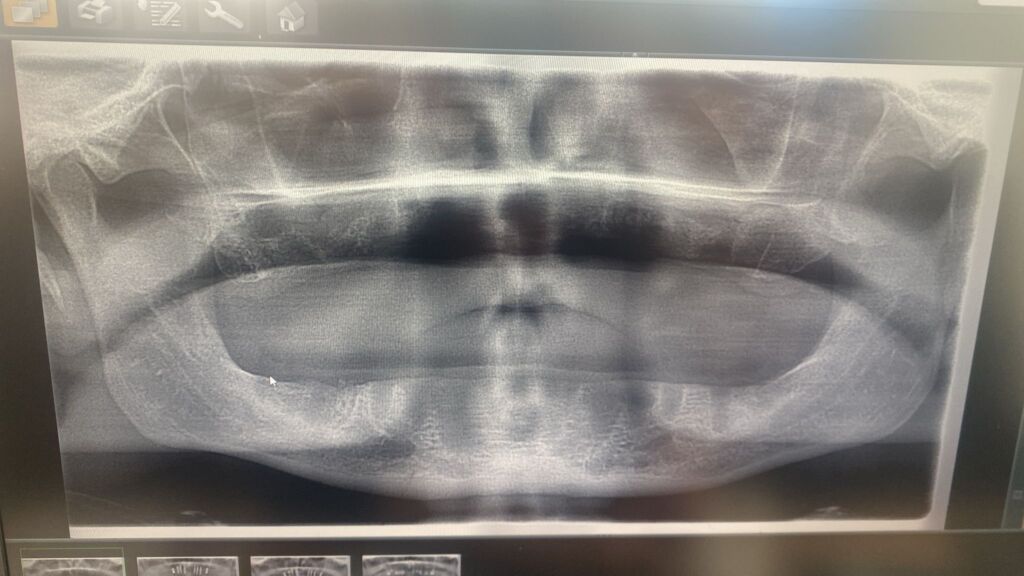

Eenmaal in de kliniek gaat het meteen extreem: zijn tanden worden volledig getrokken om plaats te maken voor implantaten. Maar waar je normaal gesproken tijdelijke tanden krijgt of een duidelijk hersteltraject, loopt het bij Denton totaal anders. De implantaten worden slecht geplaatst en beginnen al snel los te raken.

Volgens zijn eigen verhaal vielen zijn tanden er letterlijk uit, zelfs tijdens iets simpels als lachen. Wat een esthetische ingreep moest zijn, veranderde in een situatie waarin hij compleet tandeloos achterbleef. Alsof dat nog niet genoeg is, krijgt Denton ook te maken met ernstige complicaties na de operatie.

Zijn lichaam reageert slecht op de geplaatste materialen. Er is sprake van een allergische reactie, wat zorgt voor ontstekingen en extra schade aan zijn mond. Hierdoor wordt herstel nog ingewikkelder. Nieuwe implantaten plaatsen is niet zomaar een optie, en elke volgende behandeling brengt risico’s met zich mee.

Na de mislukte behandeling keert Denton terug naar het Verenigd Koninkrijk, zonder tanden en zonder directe oplossing. Britse tandartsen staan voor een lastig probleem: de schade herstellen is complex en duur, en niet alles kan zomaar worden teruggedraaid.